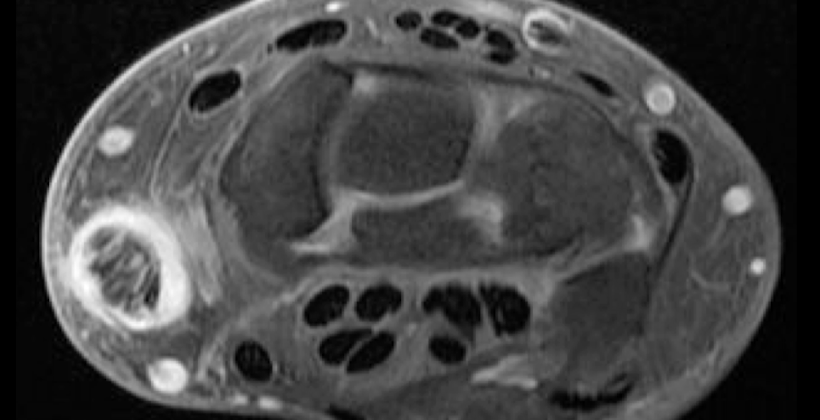

RM SxTC

Nervio aplanado hiperintenso

captación de contraste

detección de masas